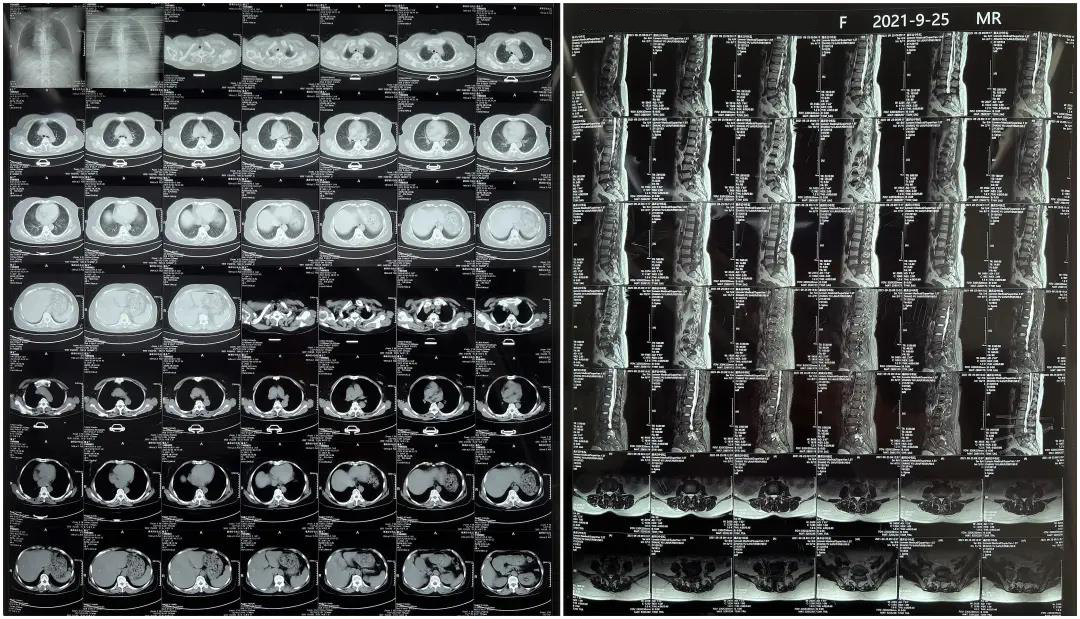

術前患者核磁共振圖像

顯示L3/4、L4/5椎間盤突出,L5-S1水平椎管內占位